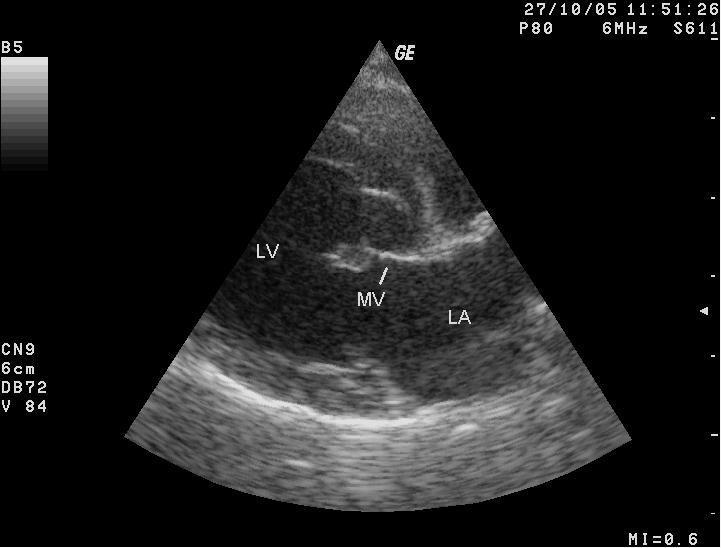

The echocardiograph examination shows the dimensions of the heart chambers, wall thickness and movement, valve movement and lesions, fractional shortening, among other characteristics. The echo screen shows the amount of wall contraction, which enables the operator to determine contractility, preload*, and afterload*. These factors are used to calculate "fractional shortening" (FS%) which is used as an indication of ventricular performance and of myocardial contractility.

(In the image at right, the red spurt of blood is shooting upward and backward, from the left ventricle, through the not-fully-closed mitral valve, back into the left atrium.)